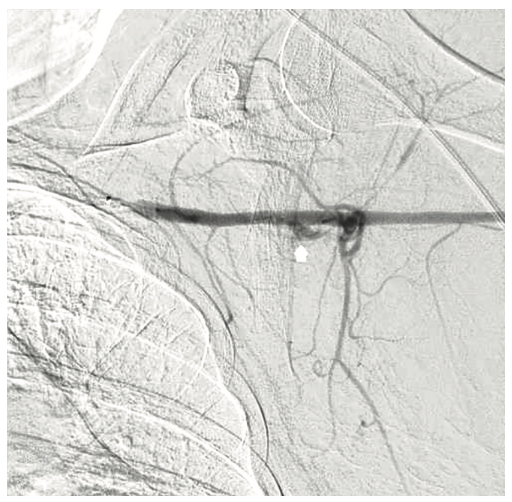

A 54-year-old female with a history of peripheral arterial disease (PAD), tobacco abuse, diabetes, severe chronic obstructive pulmonary disease (COPD), obesity, hypertension, and hyperlipidemia presented to an outside hospital with a non-ST-elevation myocardial infarction (NSTEMI). Subsequent left heart catheterization revealed a chronic total occlusion (CTO) of the left anterior descending coronary artery (LAD) and left circumflex (LCx), with a 95% ostial ramus and a patent right coronary artery (RCA) with right to left collaterals (Figures 1-2). Initial ejection fraction by ventriculogram was approximately 30-35%. She was turned down for surgery and subsequent studies revealed viable myocardium; therefore, she was scheduled for percutaneous revascularization with mechanical circulatory support using an Impella left ventricular assist device (Abiomed). She was found to have bilateral occlusion of her iliac stent (Figure 3). It was decided to revascularize at least one of her occluded iliac arteries, and then use the femoral and radial approach for dual access in order to recanalize the CTO. The axillary artery would be used for the Impella, rather than advancing the 14 French (Fr) sheath through a freshly stented artery. The right iliac artery was revascularized and she was brought back to revascularize the left system.

The right groin was accessed using fluoroscopic guidance. A micropuncture sheath was placed and upsized to a 7 French, 45 cm Destination sheath (Terumo) in the right groin. We accessed the right radial, but could not get good flow. Therefore, we ended up using the ulnar artery with ultrasound guidance and placed a Terumo 5/6 Slender sheath in the ulnar artery. We proceeded to access the left axillary artery. We placed a Judkins right (JR)4 catheter in the left subclavian and did a selective angiogram, documenting the location of the thoracoacromial artery and circumflex humeral (Figure 4); then using a Chiba biopsy needle (Cook), accessed the axillary artery and placed a 5-French 30 cm sheath (Cook)(Figure 5). We used the 15 cm biopsy needle to allow us a shallow angle of approach with the patient’s body habitus and to avoid “kinking” the sheath. We then switched out for the Lunderquist wire (Cook Medical), placed an 8 Fr sheath, and performed a pre-close using two Perclose devices (Abbott Vascular) (Figure 6).